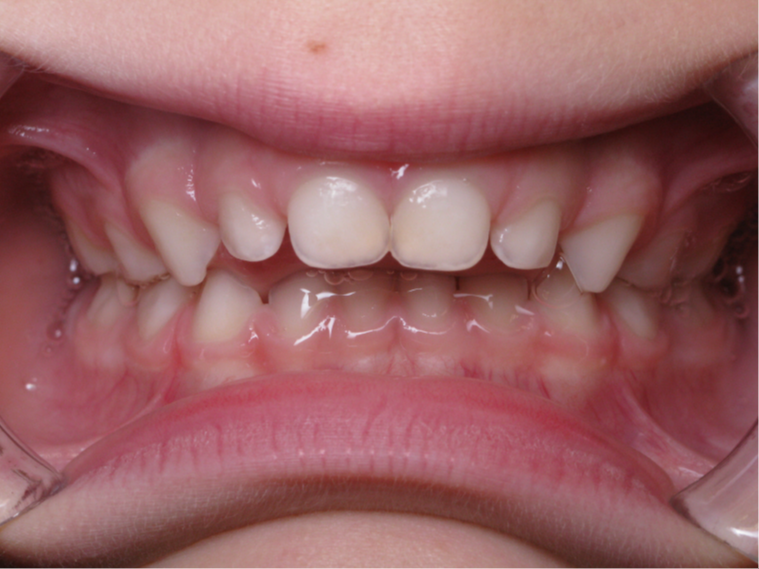

bilan début fin de traitement

Sélectionnez les différentes étapes du traitement pour comparer et analyser la dentition du cas clinique.